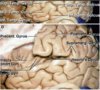

Key gyri on medial view of frontal lobe

Superior frontal gyrus

Paracentral lobule

Cingulate gyrus

Key sulci on medial surface of frontal lobe

Cingulate sulcus

Key gyri on orbital view of frontal lobe

Gyrus rectus

Medial orbital gyrus

Anterior orbital gyrus

Posterior orbital gyrus

Lateral orbital gyrus

Key sulci on orbital surface of frontal lobe

Olfactory sulcus

Orbital sulcus